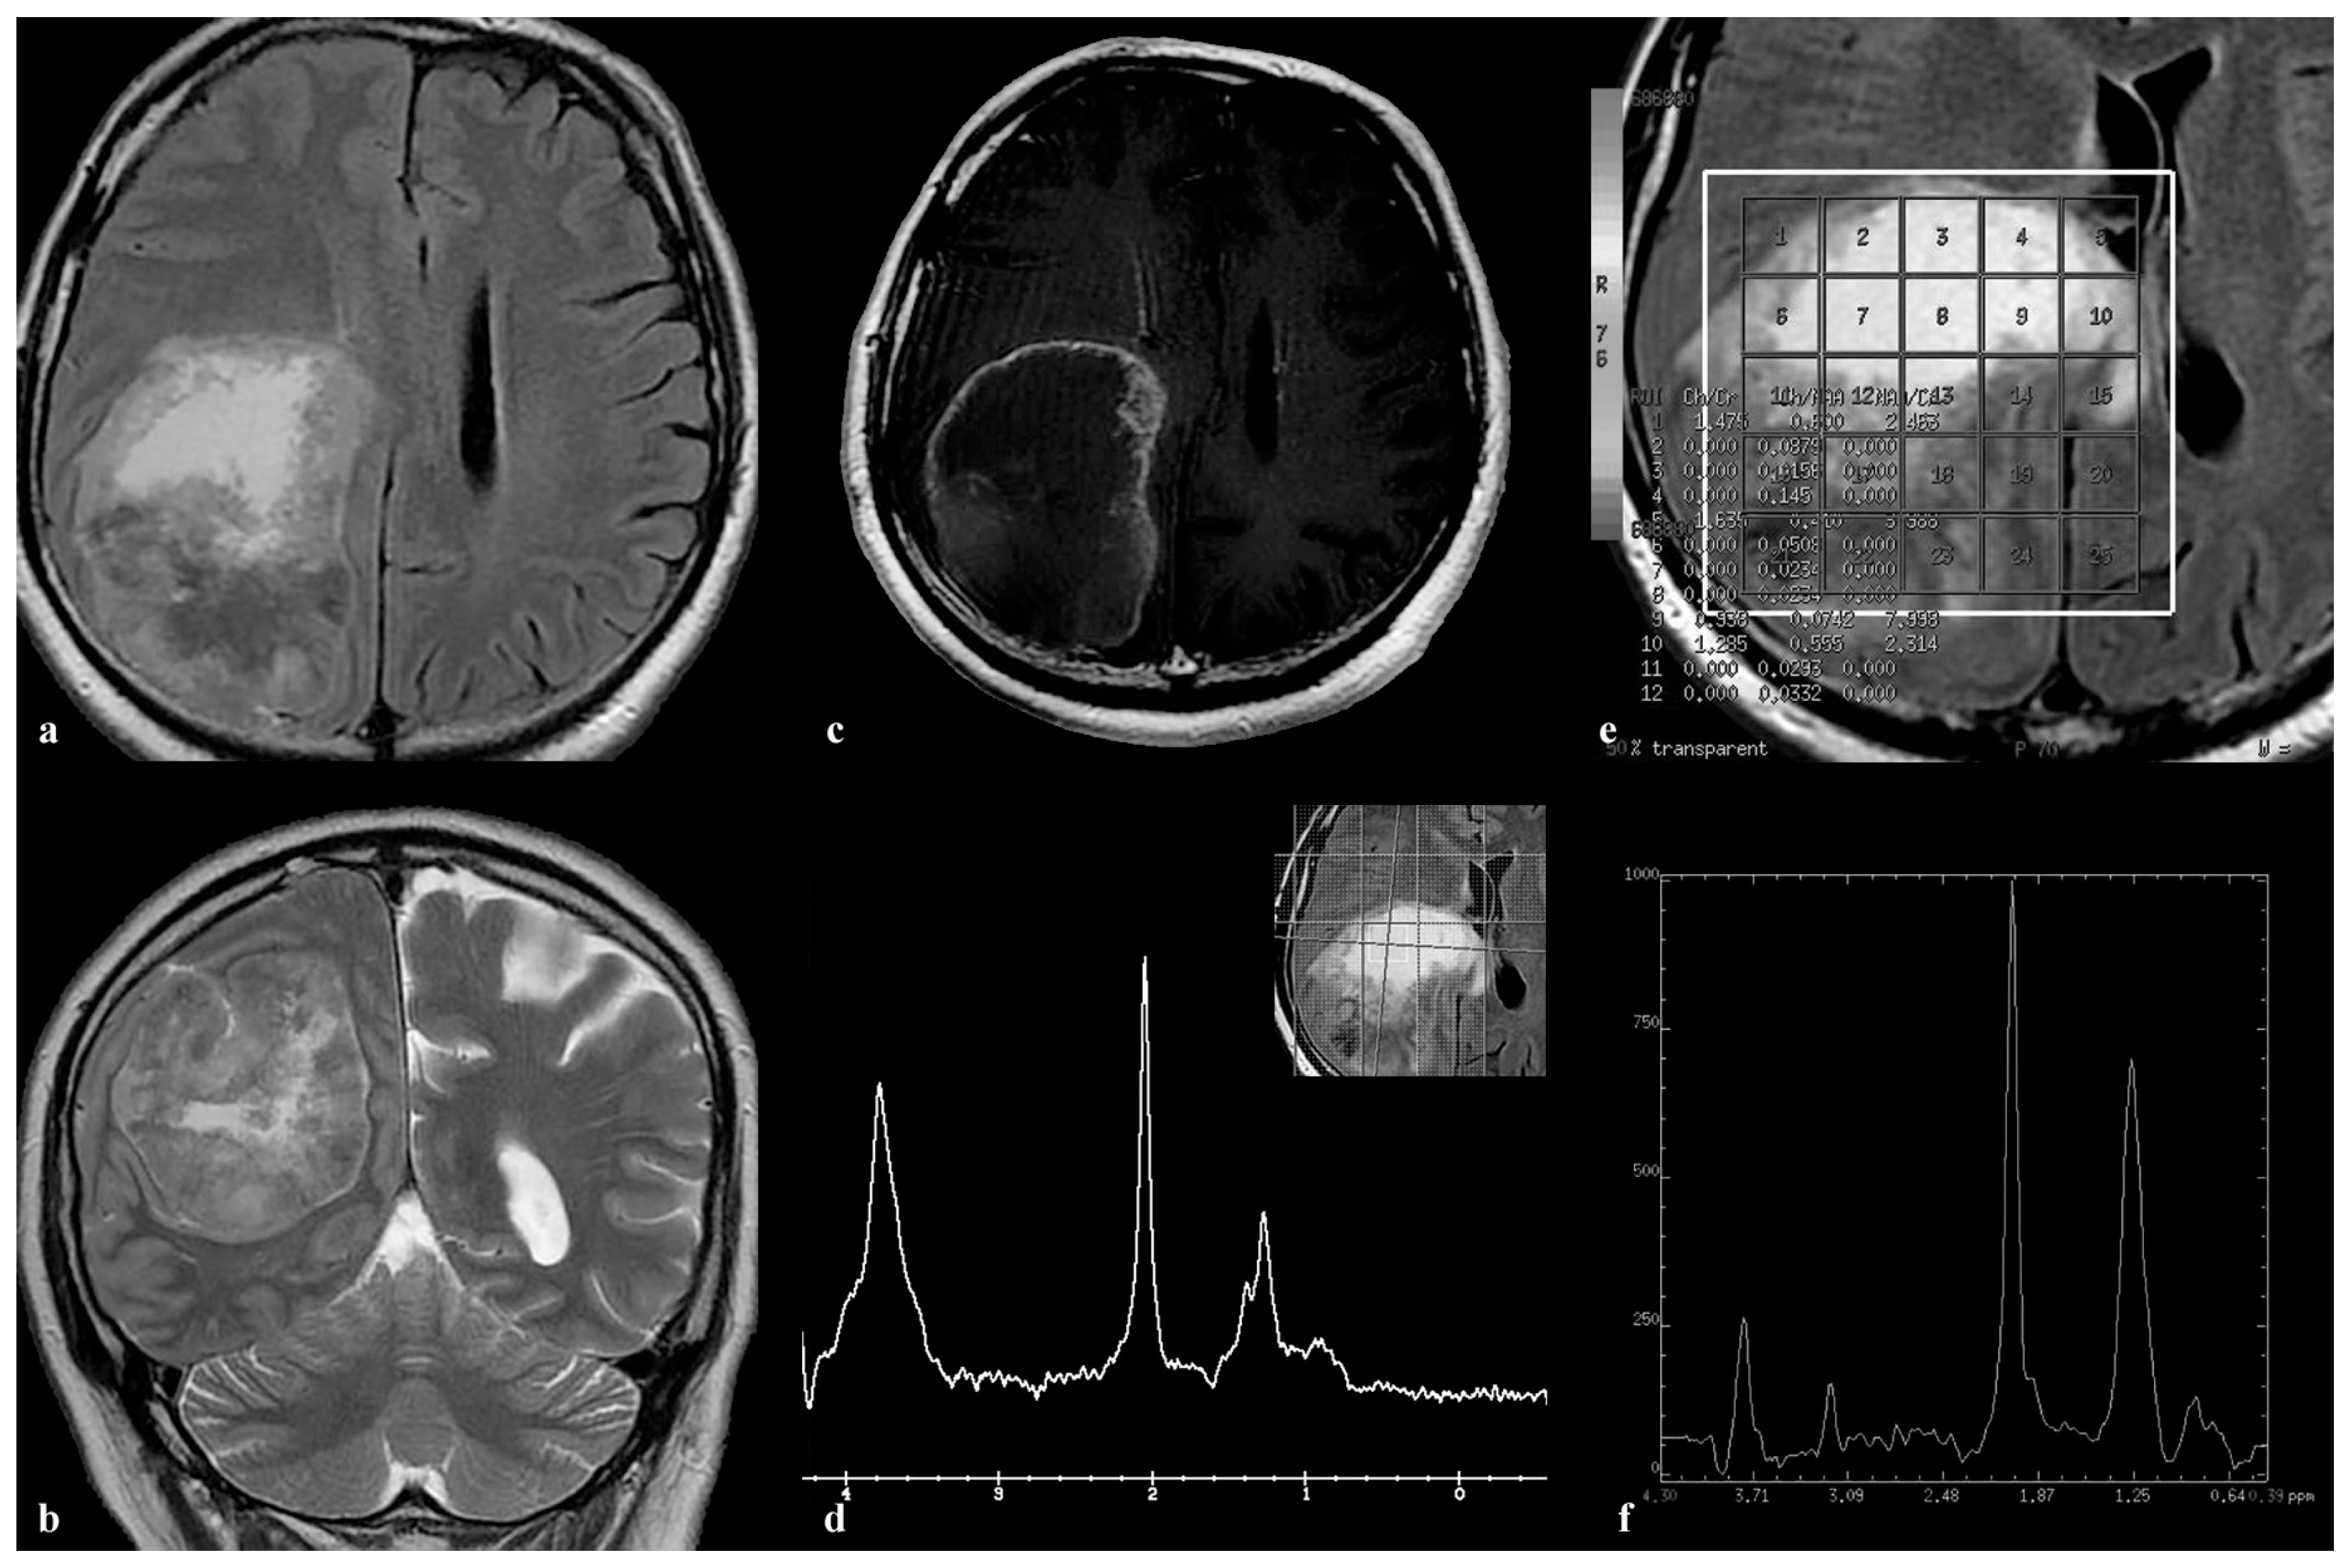

3.4. Patient 4

3.5. Patient 5